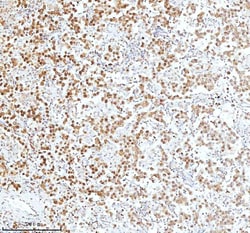

Reconstitute with 0.2 mL of distilled water to yield a concentration of 500 μg/mL. Positive Control - WB: human LNCAP whole cell, human Hela whole cell, human 293T whole cell, human HepG2 whole cell, human Jurkat whole cell, human K562 whole cell, human A549 whole cell, human A431 whole cell. IHC: human bladder cancer tissue, human bladder cancer tissue, human colon adenocarcinoma tissue, human colon adenocarcinoma tissue, human glioblastoma tissue, human glioblastoma tissue, human liver cancer tissue, human liver cancer tissue, human lung adenocarcinoma tissue, human lung adenocarcinoma tissue, human pancreas ductal adenocarcinoma tissue, human pancreas ductal adenocarcinoma tissue, human testicular seminoma tissue, human testicular seminoma tissue. ICC/IF: U2OS cell. Flow: A431 cell. Store at -20°C for one year from date of receipt. After reconstitution, at 4°C for one month. It can also be aliquotted and stored frozen at -20°C for six months. Avoid repeated freeze-thaw cycles.